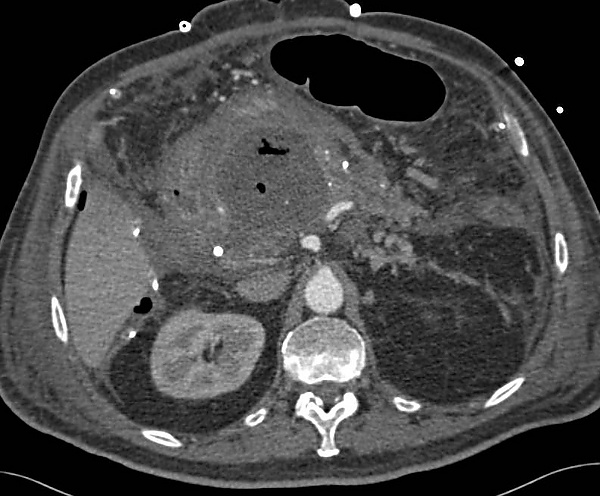

При компьютерной томографии и магнитно-резонансной томографии АПЖ характеризуется очаговым скоплением жидкости с плотной капсулой в парапанкреатической клетчатке, наличием газовых пузырей, признаками некроза, сдавлением соседних органов и реактивным выпотом[1].